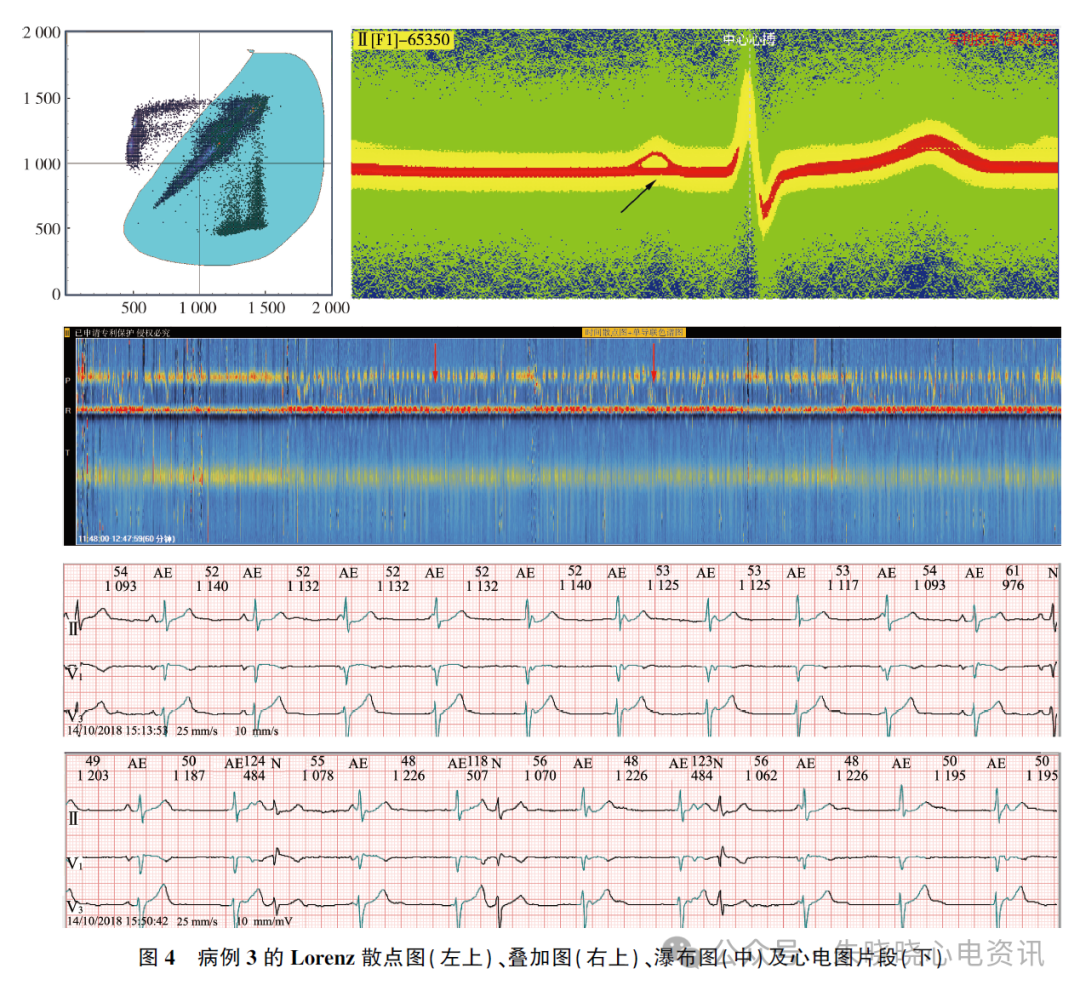

④ >1. 5 s 的长RR 间期145 次(最长1. 167 s),为显著窦性心动过缓并心律不齐、交界性逸搏周期所致;⑤ 可见大量逸搏夺获二、三联律及逸搏心律。见图4。

本例Lorenz 散点图特点是逸搏心律呈“曲尺”状图形分布于等速线的远端。

连续的窦性心律点集和连续逸搏点集均位于等速线上,逸搏-夺获点集垂直于x 轴,夺获-逸搏点集垂直于y 轴。

本例中连续的窦性心律点集和连续逸搏点集均分布于等速线上,二者有频率的重叠,所以点集也重叠交织,不易区分每种节律的比例及心搏数。

心电瀑布图上可见黄色的P 峰带(窦性心律,P波直立)和无P 峰带(交界性逸搏心律,无P 波)频繁交替出现(图4 瀑布图中红色箭头所指),说明窦性心律与交界性逸搏心律相互干扰,不时交替,形成干扰性房室脱节。

因两种节律重叠交织,此例动态心电图同病例2 一样,采用Lorenz 散点图及心电瀑布图分析也有难度,而利用叠加图在形态分析中的优势可实现两种节律快速分离。

窦性心律时有直立的P 波,交界性逸搏心律无P 波,用P 波清晰的Ⅱ导联作为分析导联,利用叠加图的切割技术将交界性逸搏心律(图4 叠加图中黑色箭头所指)波切入F2(或F3、F4)中,并全部选中,一键改为AE(交界性逸搏心律)即可实现快速分离。